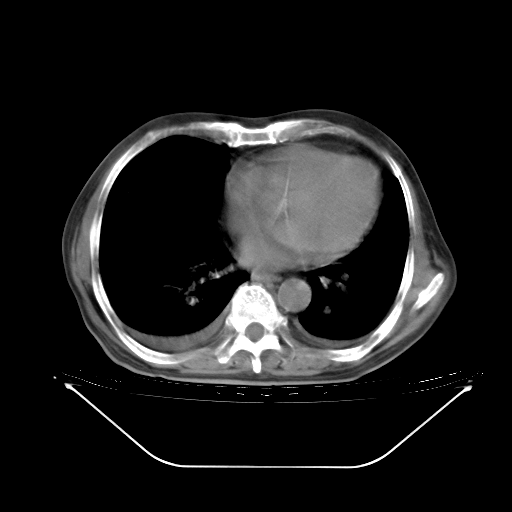

胸腹部CT,诊断意见:左上肺叶钙化灶、左侧胸膜局限性增厚并钙化、胆囊炎。描述部分肺组织呈磨玻璃样改变。

为什么又出现紫绀、呼吸加快?老人到底是什么病?我真的不甘心!但是我又能怎么办? |